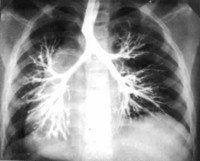

Ведущую роль в диагностике бронхоэктатической болезни у детей играет инструментальное обследование - рентгенография грудной клетки, бронхоскопия и компьютерная томография. На рентгенограмме можно определить уменьшение объема легкого, его смещение, деформацию и ячеистость легочного рисунка. Чаще поражается левое легкое. Бронхоскопия дает возможность выявить нарушение мукоцилиарного клиренса, воспалительные и структурные изменения в просвете бронха. Прямыми признаками бронхоэктатической болезни у детей на КТ являются расширение бронхов, отсутствие сужения дистальных отделов бронхиального дерева и ухудшения его видимости в краевых участках легких.